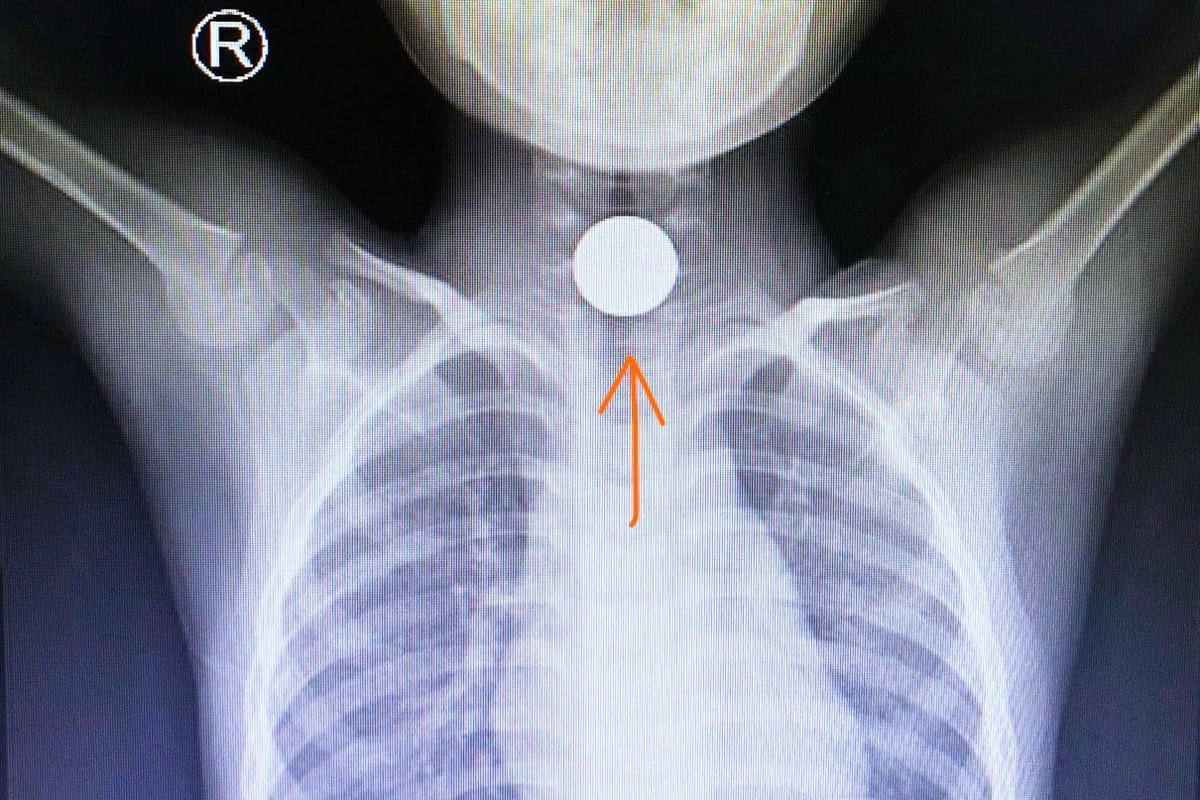

Bác sĩ Nguyễn Cát Phương Vũ, Bệnh viện Nhi đồng Thành phố (TP HCM) cho biết, vừa cứu kịp thời một bệnh nhi bị hóc dị vật rất nguy hiểm ngay trong ngày đầu năm mới. Bệnh nhi là một bé trai 5 tuổi, nhập viện trong tình trạng có dị vật mắc ngang chặn bít thực quản đoạn trên.

Khai thác bệnh sử, trước đó bé cùng cha mẹ sang nhà họ hàng mừng tuổi chúc Tết. Trong lúc nô đùa cùng các anh em, bạn bè cùng trang lứa, bé lấy đồng xu ngậm chơi rồi bất ngờ nuốt và nghẹn ở cổ họng. Phát hiện sự việc và thấy con ho sặc sụa liên tục, cha mẹ bé hốt hoảng đưa con đi cấp cứu.

Tại bệnh viện nhờ chẩn đoán và phát hiện dị vật sớm, bác sĩ Lê Đức Lộc, trưởng ekip nội soi đã cùng cộng sự tiến hành gắp dị vật thành công, lấy đồng xu ra khỏi thực quản bệnh nhi.